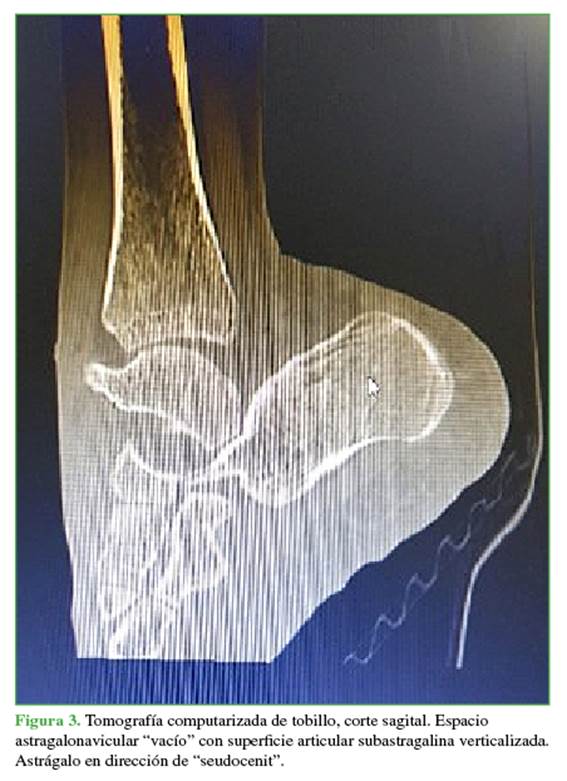

Se tomaron radiografías anteroposterior y lateral de tobillo que mostraron la pérdida de la relación articular del astrágalo con luxación astragalocalcánea posterior, luxación astragalonavicular con preservación de las relaciones articulares tibioastragalina y calcaneocuboidea sin fractura del cuello del astrágalo. La tomografía computarizada como estudio complementario no reveló lesiones asociadas no evidentes (Figuras 2 y 3).